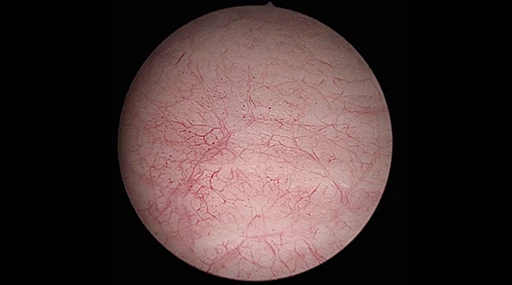

Selezione della modalità direttamente sulla testa della telecamera – visione migliore per una maggiore efficienza

Grazie ai pulsanti di comando liberamente assegnabili, è possibile selezionare la funzione desiderata in modo ancora più comodo e intuitivo. Con la semplice pressione di un pulsante, AlphaSMART consente di vedere esattamente ciò che si desidera utilizzare in qualsiasi momento.

In combinazione con il mascheramento intelligente delle influenze di distrazione e il pieno utilizzo delle opzioni di ottimizzazione dell’immagine, ciò consente decisioni più sicure e risultati più rapidi, grazie a informazioni chiare e mirate.

Miglioramento selettivo del colore (SCE)

Senza SCE

Le strutture e i vasi sono appena visibili.

Con SCE

Migliore visibilità delle strutture e delle imbarcazioni, aspetto naturale preservato.

Riduzione del fumo

Senza riduzione del fumo

Visibilità oscurata a causa della nebbia e del fumo.

Con riduzione del fumo

Migliore visibilità durante l’uso di strumenti HF/RF.

Cambiamento di colore (CS1 / CS2)

Senza cambiamento di colore (CS1 / CS2)

Strutture e imbarcazioni sono appena visibili, molte sfumature di rosso.

Con Color Shift (CS1 / CS2)

Migliore visibilità delle strutture e dei vasi, riduzione delle sfumature di rosso, colori fortemente contrastati.

Autolight

Senza Autolight

Possono verificarsi incongruenze nell’illuminazione, con potenziali ripercussioni sulla precisione e necessità di regolazioni manuali.

Con Autolight

Il sistema regola automaticamente l’illuminazione per garantire un’illuminazione costante durante tutta la procedura.